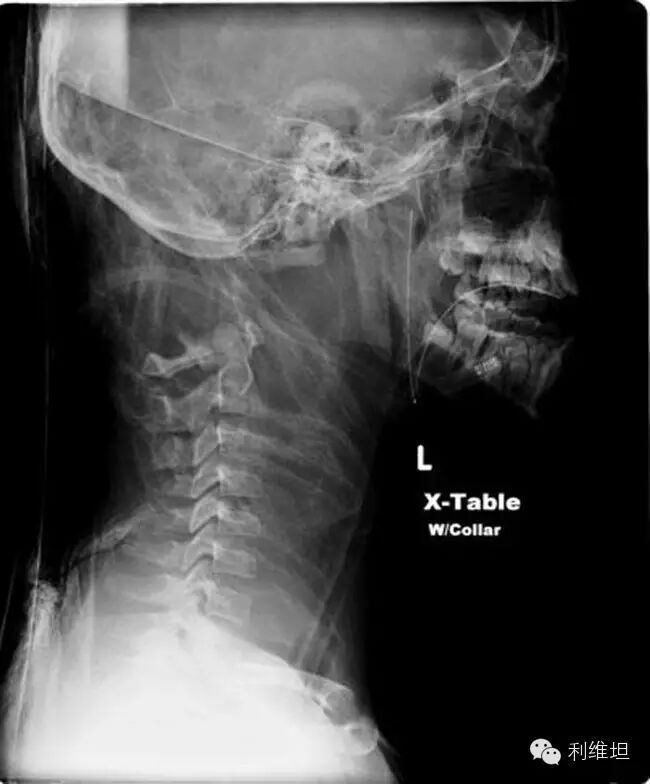

外力导致身体和头分开是我们最熟悉的斩首方式,但是其实还有更有趣少见的体内断头。体内斩首的意思是人的头骨和脊椎分开,但是身体和头还是连在一起的。通常是因为遭遇意外或头部受到重击。像是上吊的绞刑就是利用体内断头的方式确保罪犯死得很快。